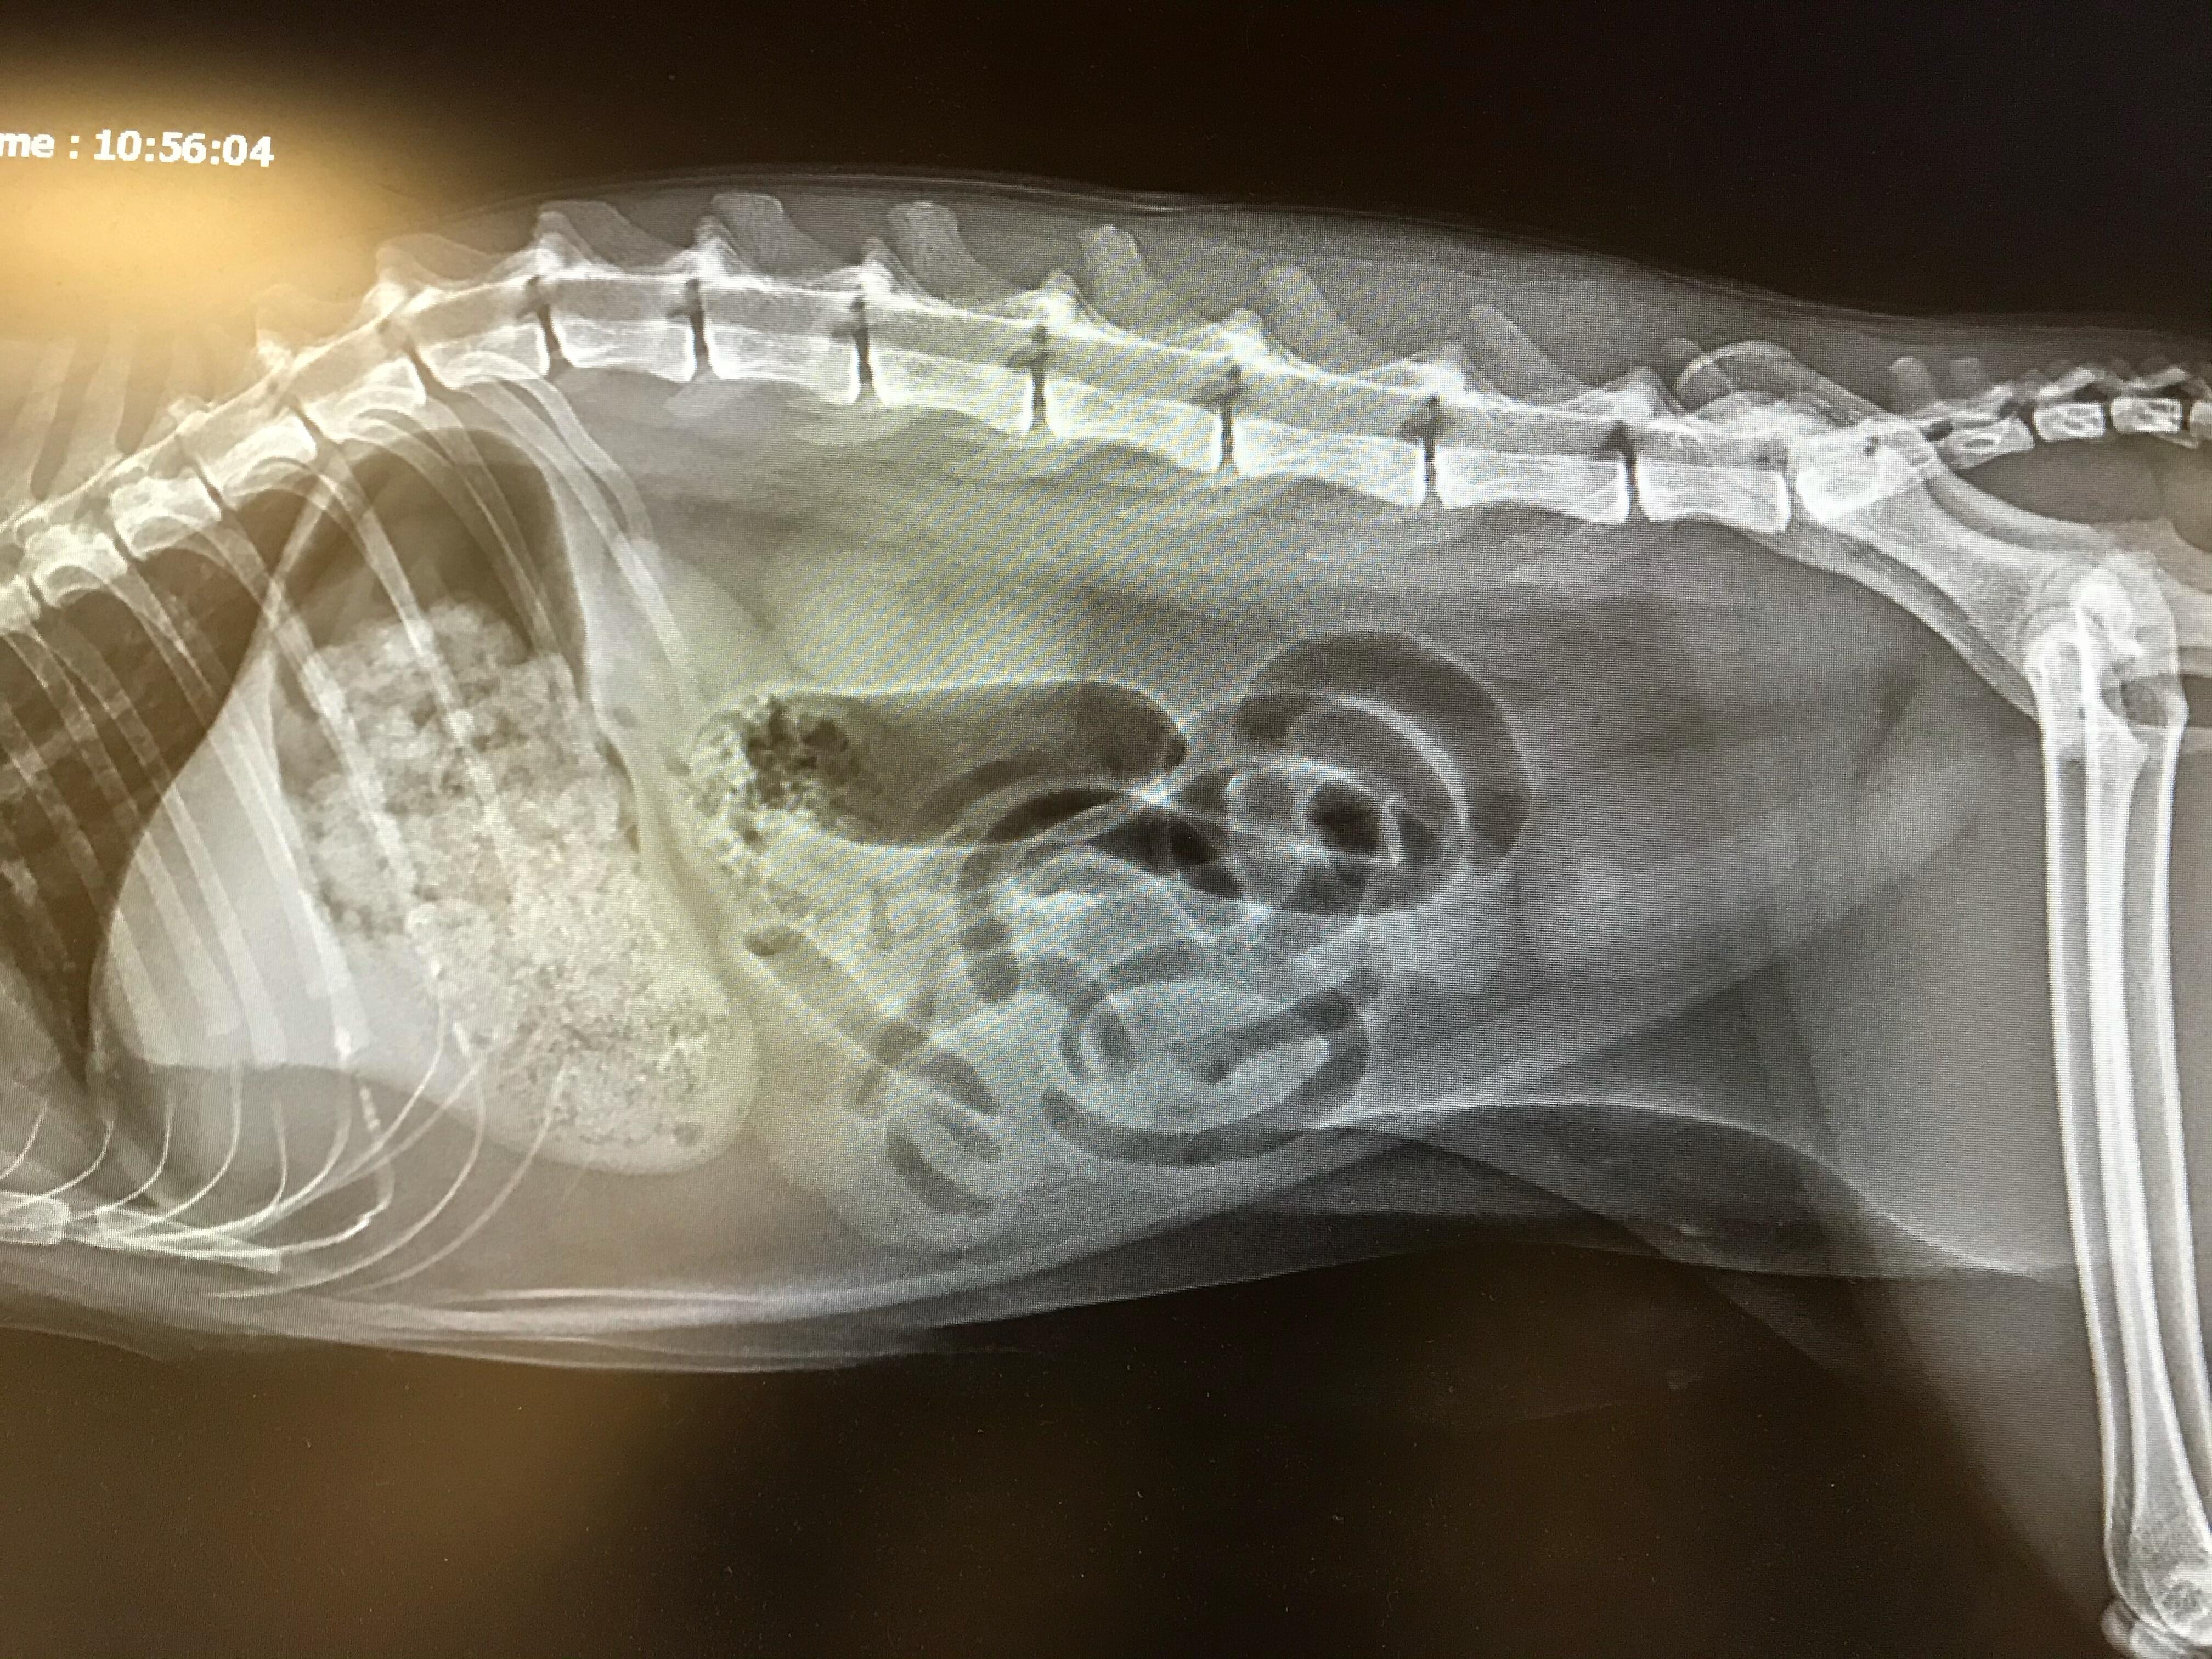

Pet's info: Cat | Mixed Breed | Male | neutered | 2 years and 3 months old | 11 lbs

If my cat were to start a diet of Hill's® Prescription Diet® c/d Multicare Urinary Care Stress Cat Food, could this bladder stone break up/dissolve and pass?

I'm sorry to see that Beau has this large bladder stone! The most common types of bladder stones in cats are struvite and calcium oxalate, but the only surefire way to differentiate between the two is with a stone analysis after the stone has been surgically removed. The Hill's C/D multicare can dissolve some struvite stones, but will not dissolve calcium oxalate stones. For the long term, however, this diet is fantastic at preventing a recurrence of such bladder stones and crystals. It's a bit of a gamble using a diet to dissolve stones, particularly in male cats, because of the potential of part of the stone breaking off and causing a urinary obstruction, or blockage, as this is a life-threatening emergency. I generally find it to be safest and most effective to remove bladder stones surgically since you know that it's going to work right away without the same obstruction risks. I hope that everything goes well for Beau!